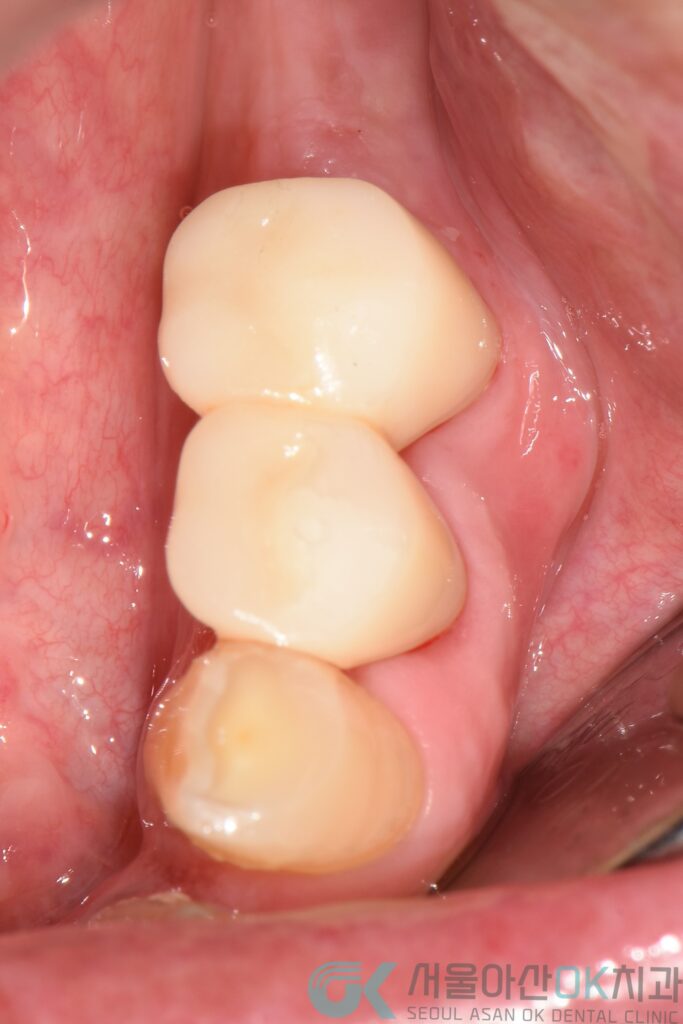

마지막은, 더 이상 버티기 힘든 치아를 대신하는 선택입니다.

예후가 좋지 않은 치아는

깔끔하게 발치하고,

그 자리는 임플란트로 단계적으로 회복했습니다.

골 상태에 따라

충분한 치유 시간을 확보하고,

안정성이 확인된 후에

최종 보철까지 마무리했습니다.